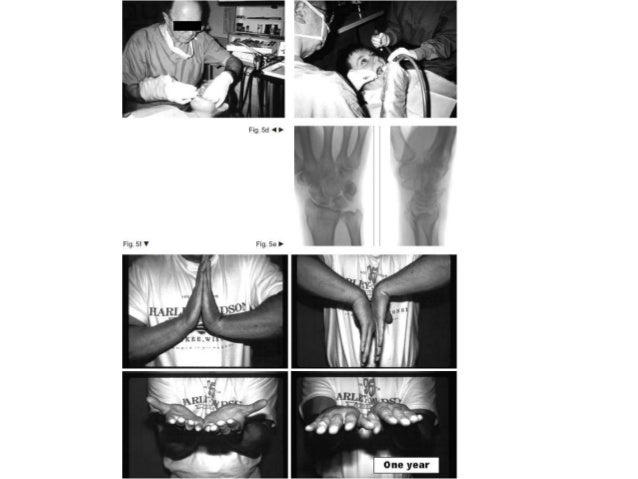

Distal radius fracture management in elderly patients remains without consensus regarding the appropriate treatment or anticipated outcome. Forty-one Estimated Reading Time: 10 mins  · Review Abstract Distal radius fracture management in elderly patients remains without consensus regarding the appropriate treatment or anticipated outcome. Forty-one studies that included at least 10 patients with a minimum mean age of 65 years and that were indexed in Medline or Embase were reviewed  · Registered 27/09/—retrospectively registered. blogger.com Introduction Distal radius fracture (DRF) is one of the most common fractures of upper

We found no clear evidence of the clinical superiority of distal radius fracture surgery among older adults at one blogger.comal treatment, however, may yield a faster recovery to previous level of activity in elderly blogger.com operative treatment, hardware-based problems may warrant secondary operations and implant removal, whereas in non-operative treatment, Chung et al systematically reviewed the current literature for the treatment options of DRFs in patients over the age of 60 years treated with 5 common techniques: volar locking plate system, nonbriding EF, bridging EF, percutaneous K-wire fixation, and cast immobilization. 1 The authors concluded that despite worse radiographic results in the group with cast  · Review Abstract Distal radius fracture management in elderly patients remains without consensus regarding the appropriate treatment or anticipated outcome. Forty-one studies that included at least 10 patients with a minimum mean age of 65 years and that were indexed in Medline or Embase were reviewed

We found no clear evidence of the clinical superiority of distal radius fracture surgery among older adults at one blogger.comal treatment, however, may yield a faster recovery to previous level of activity in elderly blogger.com operative treatment, hardware-based problems may warrant secondary operations and implant removal, whereas in non-operative treatment,  · Increasing numbers of distal radius fractures in elderly patients with greater functional demands led us to review the existing literature on its management. This effort included randomized clinical trials, prospective cohort studies, and retrospective reviews that included at least 10 patients with a minimum mean age of 65 years and that were published Author: Sebastian V. Gehrmann, Joachim Windolf, Robert A. Kaufmann Stratifying patients into low-demand and high-demand groups may improve the management of distal radius fractures in elderly patients. In sedentary patients with low demands, functional outcomes are good despite the presence of deformity. Patients with higher demands may benefit from fracture stabilization with locking volar blogger.com: Sebastian V. Gehrmann, Joachim Windolf, Robert A. Kaufmann

Stratifying patients into low-demand and high-demand groups may improve the management of distal radius fractures in elderly patients. In sedentary patients with low demands, functional outcomes are good despite the presence of deformity. Patients with higher demands may benefit from fracture stabilization with locking volar blogger.com: Sebastian V. Gehrmann, Joachim Windolf, Robert A. Kaufmann Distal radius fracture management in elderly patients remains without consensus regarding the appropriate treatment or anticipated outcome. Forty-one Estimated Reading Time: 10 mins Epidemiology of Elderly Distal Radius Fractures • Most common upper extremity fracture (16%) • Second most common overall fracture in elderly patients (18%), after hip fractures • Incidence is increasing, especially in patients older than 65 • 15% of white women will fracture their distal radius after age 50 CoreCurriculumV5